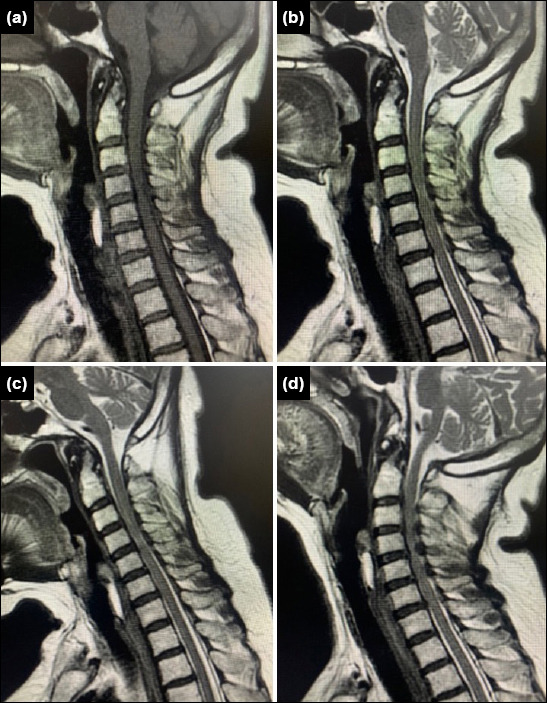

Methods: We retrospectively analyzed patients who underwent cervical subaxial pedicle screw placement between 2017 and 2024. A freehand surgical technique was employed, using a mini-laminotomy approach to ensure safe screw placement. During the procedure, the medial, superior, and inferior borders of the pedicle were palpated.

Results: A total of 70 cases were analyzed retrospectively. Fifty patients were male, and 20 were female. The patients ranged in age from 20 to 89 years (median age: 64 years). Fifty-seven patients (81.5%) had cervical stenosis as the surgical indication. Of the remaining cases, 11 patients had fractures and two had tumors. Among the 468 pedicle screws placed, 434 were graded as 0-1. The correct placement rate was 92.7%. Thirty-four screws were malpositioned (grade 2-3), representing a rate of 7.3%.